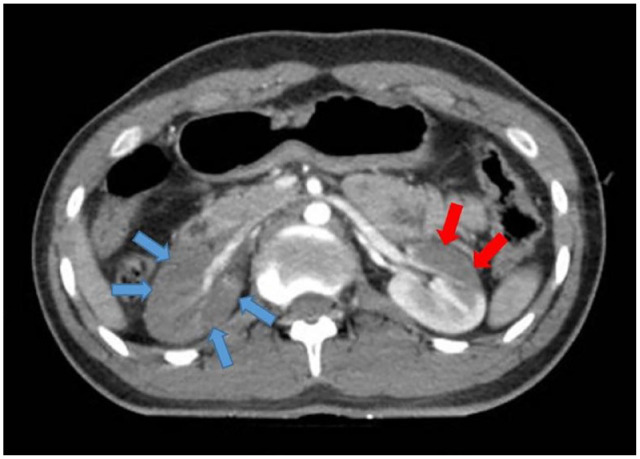

Case presentation: We report a case of 21-year-old man falling from a height of 9 m. A contrast-enhanced CT scan in the nephrogram phase showed no evidence of absorption in the right kidney and significantly decreased absorption in the left kidney. The pyelogram phase showed no secretion in the right kidney and decreased secretion in the left kidney suggesting segmental renal infarction. Subsequently, heparin infusion was initiated immediately. A follow-up contrast- enhanced abdominopelvic CT scan was performed after 1 month and showed no sign of infarction, and all laboratory tests were normal.